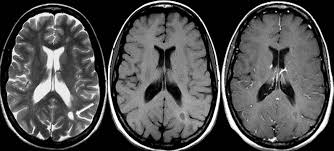

Recomiendan suspender la comercialización en Europa de algunos contrastes con gadolinio

El área de farmacovigilancia de la Agencia Europea de Medicamentos encuentra evidencia de depósitos de gadolinio en el sistema nervioso, aunque no están bien definidas sus consecuencias. EMA, 10 de marzo de 2017